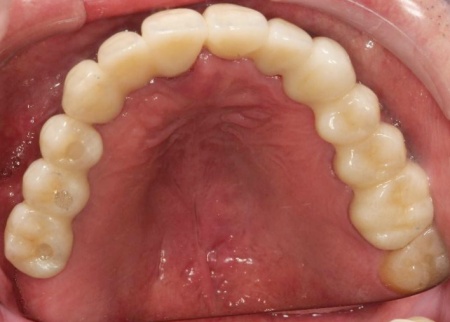

インプラントが骨にしっかりとなじんだことを確認したら、白くて強度の高い人工歯「ジルコニアクラウン」を装着しました。

また、インプラント治療と並行して、合わなくなっていた被せ物・詰め物・既存のインプラントを作り替えます。

左上奥歯は、装着されていた金属の古い詰め物を外し、白い樹脂を直接詰める「ダイレクトボンディング」で修復しました。

他院で治療を行った左下奥歯3本のインプラントは、土台をそのまま活かして人工歯だけ作り直し、噛み合わせを調整します。

左下奥歯1本、右下奥歯2本に装着されていた古い被せ物はすべて外し、ジルコニアクラウンと交換しました。

最後に、見た目や噛み合わせに問題がないかを確認し、治療を終了しています。